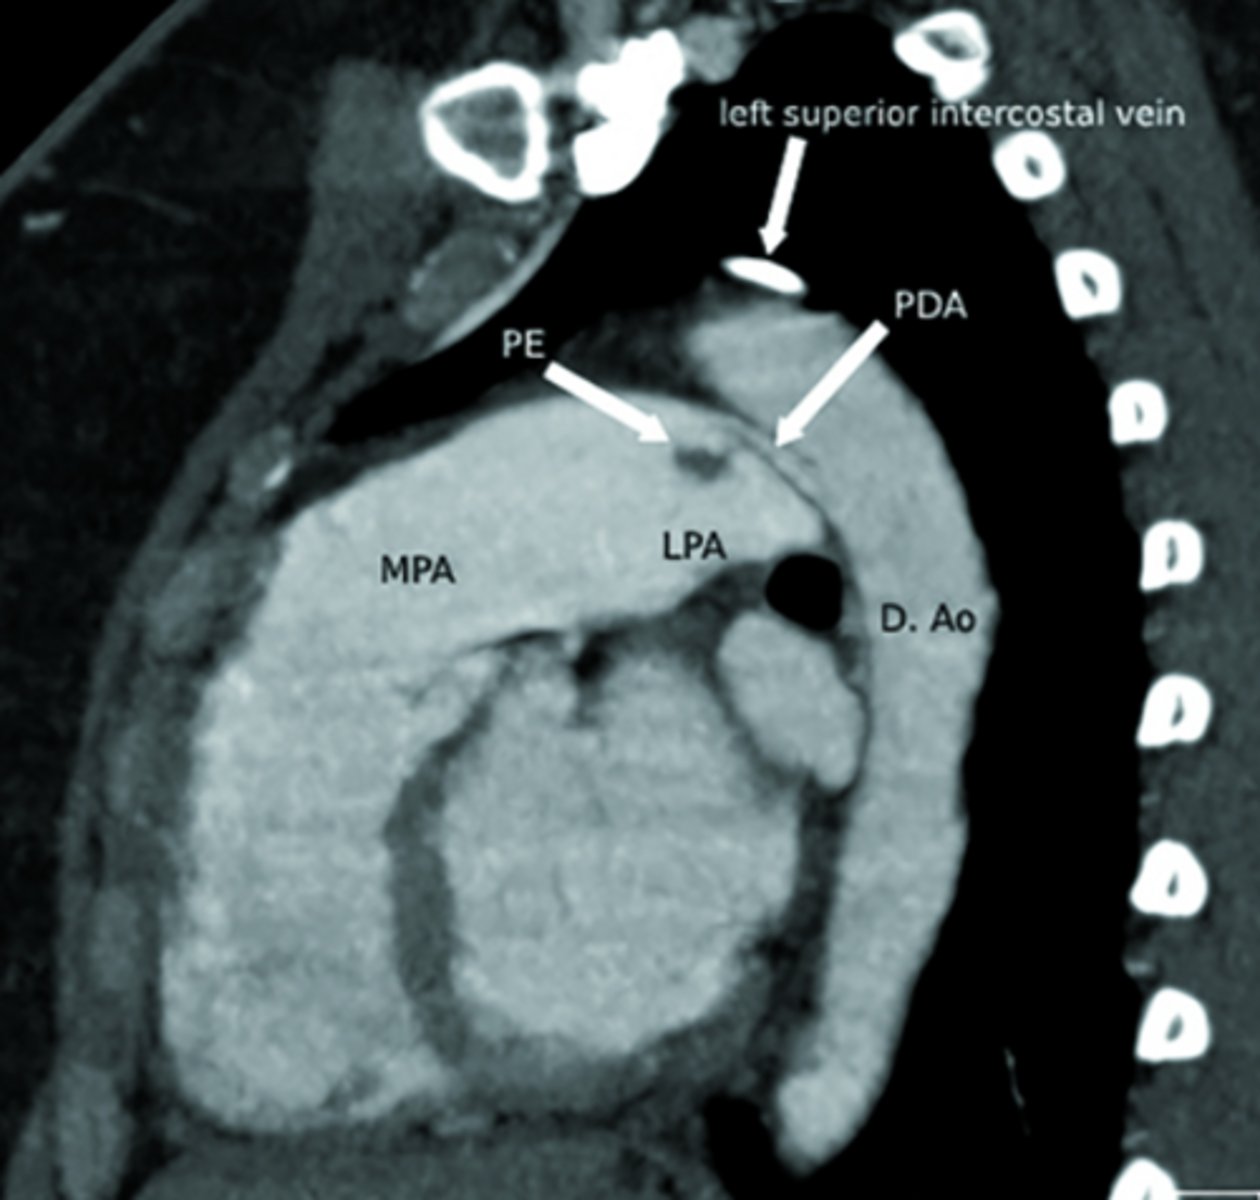

Ductus arteriosus

What is the ductus arteriosus?

A structure in embryo connecting the pulmonary trunk to the aorta.

Acts as a shunt - prevents blood from going back to lungs and instead dumps it back into aorta.

Patent ductus arteriosus

What is patent ductus arteriosus (PDA)?

Persistent connection between the pulmonary artery and aorta after birth.